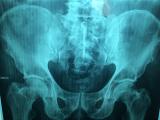

В медицинский центр «Наири» обратился мужчина 1951 года рождения с двусторонним анкилозирующим коксартрозом и ожирением первой степени. Пациент жаловался на боли, носящие постоянный характер...